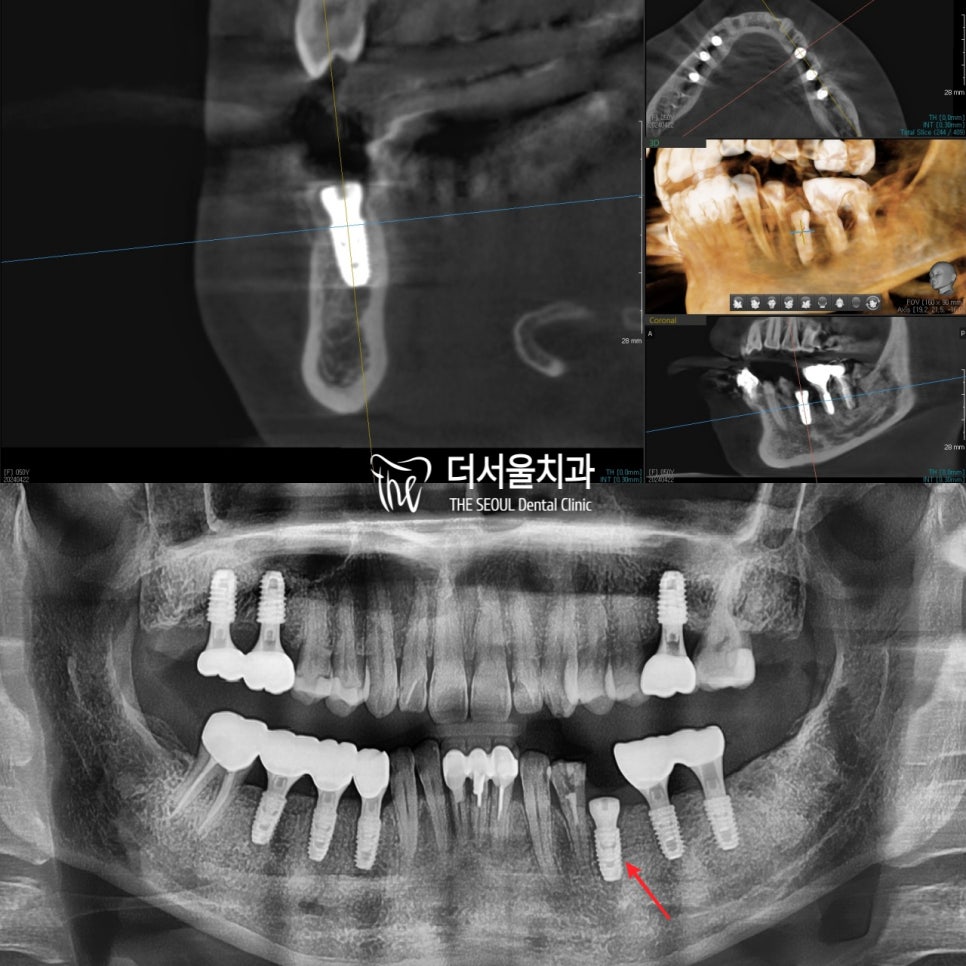

x-ray를 확대해서 찍은 사진을 보면

크라운 주변으로 거뭇거뭇한 느낌을 볼 수 있는데요.

이게 바로 이차우식증입니다.

크라운 주변으로 충치가 진행된 것입니다.

생각보다 많이 진행이 되다 보니

크라운이 옆으로 누운 걸 관찰할 수 있었습니다.

또 잇몸뼈도 많이 내려가

뿌리 끝만 붙잡고 있으니

흔들리고 있었습니다.

식립 후 파노라마 x-ray 및 CT를 확인해보면

정확한 식립을 볼 수 있는데요.